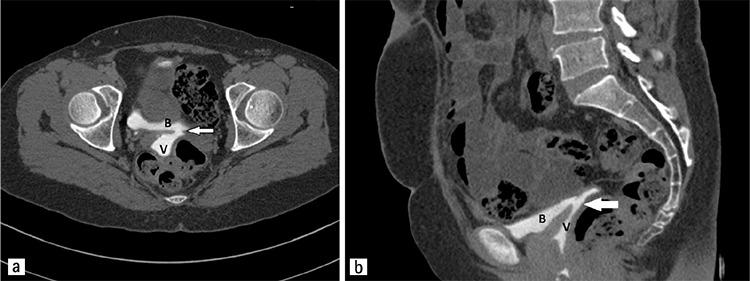

In developed nations, surgery, especially gynecologic procedures, is the major cause of vesicovaginal fistulas (VVFs). We retrospectively evaluated our treatment modalities for VVF repair caused by a gynecologic surgery, and discussed the reasons of selecting certain surgical techniques and their outcomes.

We compared the surgical procedure preferences of surgeons and their results with patient and surgeon characteristics for the management of VVFs after an inciting gynecologic surgery in Süleyman Demirel University Hospital, Isparta over a 10-year period. The surgical procedures were undertaken in departments of urology and obstetrics and gynecology.

Abdominal repair was chosen for 65%, vaginal repair for 25%, and laparoscopic repair for 10% of patients. For the 75% of the patients that urologists operated, they chose the abdominal route. The mean parity number of patients who underwent abdominal repair was lower than that for vaginal repairs (p<0.05). For the patients managed with the vaginal route, 20% had a Martius flap, and 80% had a simple excision and repair. For patients operated via the abdominal route, 18% needed omental flap; no tissue interposition was used for the rest. The mean hospitalization time was less in patients managed with transvaginal repair (3.4 days) compared with transabdominal repair (9.2 days) (p<0.05).

The choice of repair method depends on surgeon's training (gynecology vs. urology). The vaginal route should be the first choice because it does not compromise the success rate and the mean hospitalization time is less. For the transvaginal approach, access to the lesion is the most important factor for the success of the procedure. No flap is needed for tissues that appear well vascularized.